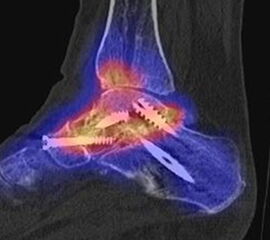

Beispiele für SPECT/CT-Untersuchungen nach OSG-TEP sind in den Abbildungen 6.1. bis 6.3. abgebildet.

Abbildung 8.6. a bis f: Patientin mit Z. n. Talusfraktur vor 2 Jahren, welche mit zwei Schrauben osteosynthetisch versorgt wurde. Seither progrediente Schmerzen im linken Fuß. Ein MRT 8 Monate vor der SPECT/CT-Untersuchung war nicht eindeutig bzw. nicht wegweisend. Im SPECT/CT aktivierte posttraumatische osteochondrale Läsion talusseitig im linken unteren Sprunggelenk mit einem abgrenzbaren Ossikel bis 5 mm Größe und angrenzenden arthrotischen Veränderungen. Reizlose Schrauben im linken Talus.